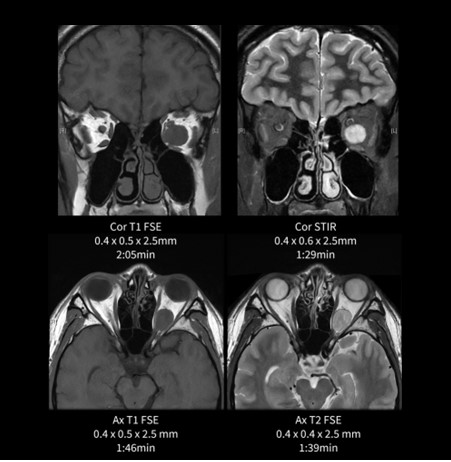

眼窩(眼窩内腫瘍)

眼窩は32-Channel Head Coilで撮像している。FOV15cmでスライス厚も2.5mmと高分解能な撮像条件であるが、SNRは十分に担保されつつ、腫瘍と視神経や内直筋、外直筋との位置関係も明瞭に描出されている。注目していただきたい画像はCoronal STIRである。STIRはSNRが下がりやすいシーケンスの一つであるが、AIR™ Recon DLのおかげでノイズも目立たずに短時間で撮像することができた。

図3.眼窩(眼窩内腫瘍)